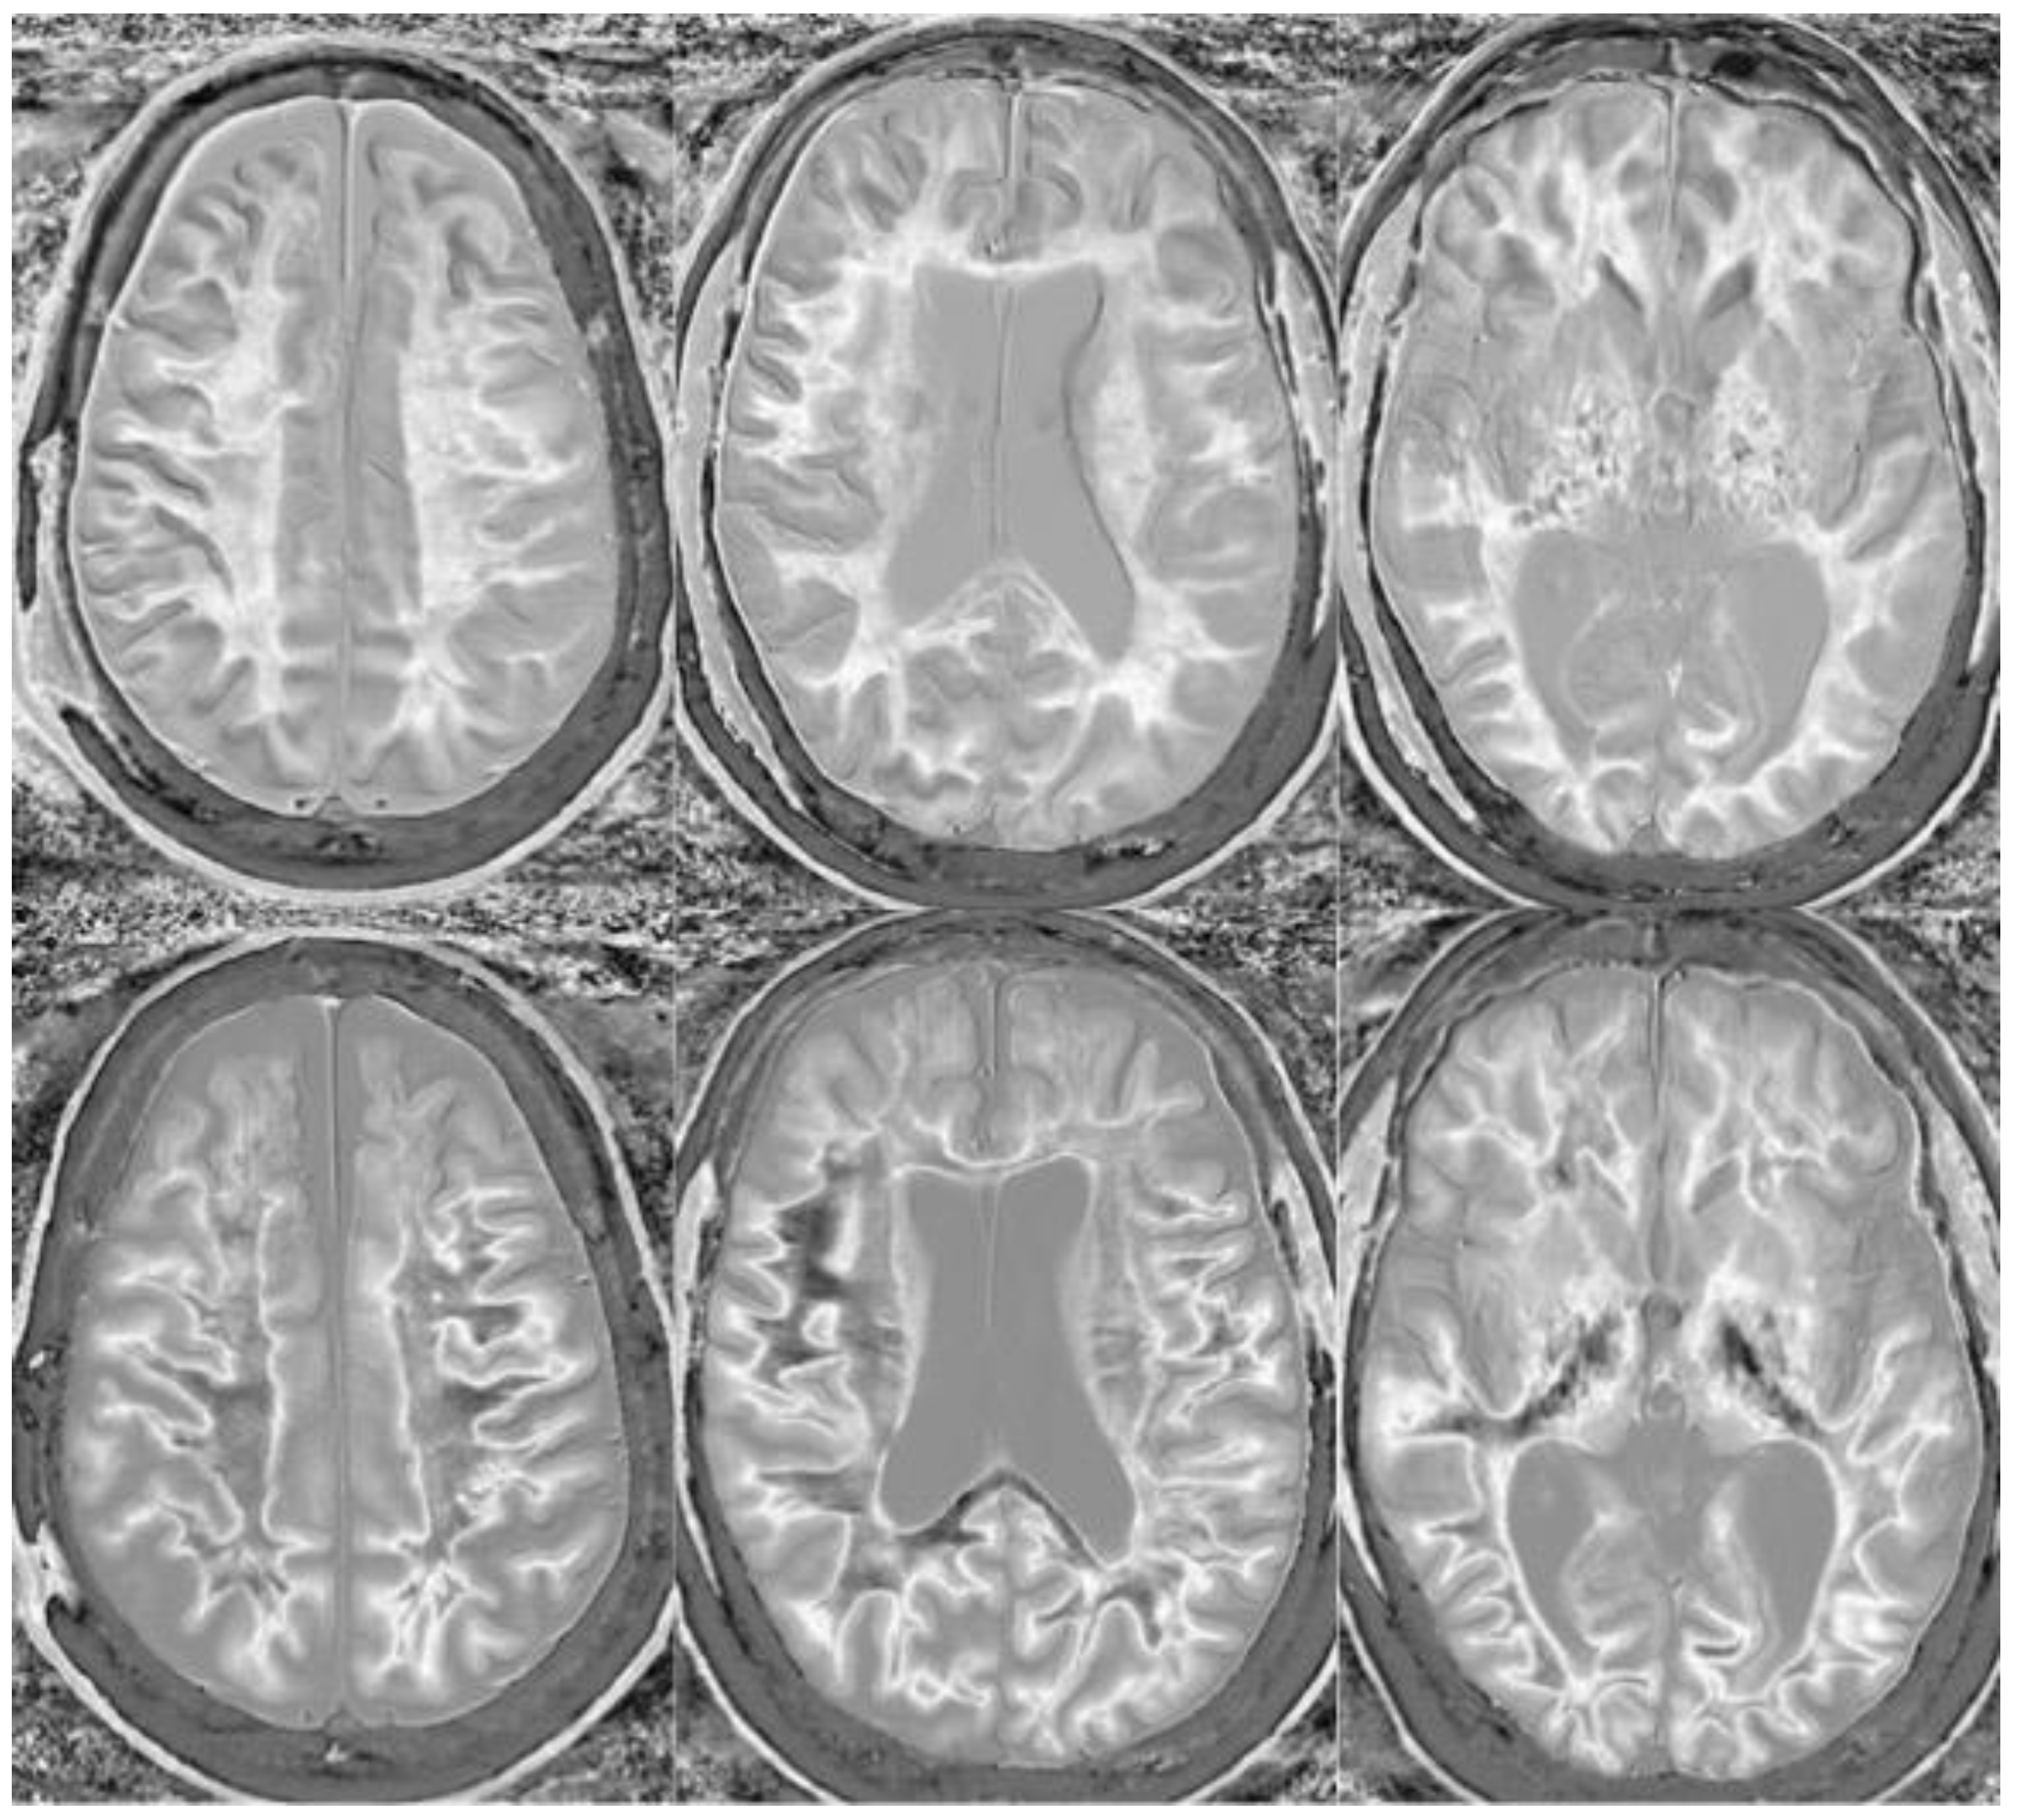

Figure 14.

Normal and abnormal divided Subtracted Inversion Recovery (dSIR) images. Narrow middle domain images in three patients at the level of the centrum semiovale. TIshort = 350 ms. TIlong = 500 ms. TE = 7 ms, TR = 5000 ms. The left image shows an example of the “white out sign”, with a diffusely increased signal throughout the white matter. The center image is an example of normal. The white matter has a mildly increased signal that is normal because TIshort = 350 ms nulls tissue with T1 values less than that of white matter. The image on the right has an intermediate appearance, probably abnormal but not a “white out”.

Divided Subtracted Inversion Recovery (dSIR) in a patient with Grinker’s myelinopathy. Top row: Narrow middle domain dSIR images at the level of the centrum semiovale (left), corona radiata (middle), and basal ganglia (right) in a patient with persistent symptoms following prolonged hypoxia due to a suicide attempt. TIshort = 350 ms. TIlong = 500 ms. TE = 7 ms, TR = 5000 ms. There is a diffuse “white out”. Bottom row: T2-FLAIR images at matching levels show normal-appearing white matter. Scans were obtained 9 months following injury.

Figure 16.

Divided Subtracted Inversion Recovery (dSIR) in a patient with Grinker’s myelinopathy. Top row: Narrow middle domain dSIR images at the level of the centrum semiovale (left), corona radiata (middle), and basal ganglia (right) in a patient with persistent symptoms following prolonged hypoxia due to drug overdose. TIshort = 350 ms. TIlong = 500 ms. TE = 7 ms, TR = 5000 ms. There is widespread “white out”, with some sparing in the deep frontal lobe white matter. Bottom row: T2-FLAIR images at matching levels show normal-appearing white matter. Scans were obtained 2 years following injury.

Figure 17.

Two boys with mild head trauma. Top row: Narrow middle domain divided Subtracted Inversion Recovery (dSIR) images at the level of the centrum semiovale (left), corona radiata (middle), and basal ganglia (right) in two young men experiencing mild head trauma in the same rugby match. TIshort = 350 ms. TIlong = 500 ms. TE = 7 ms, TR = 5000 ms. Images were obtained within 5 days of injury. The player shown in the top row had symptoms of concussion at the time of imaging, and a “white out” sign is present. The player shown in the bottom row was asymptomatic, and the images appear normal.